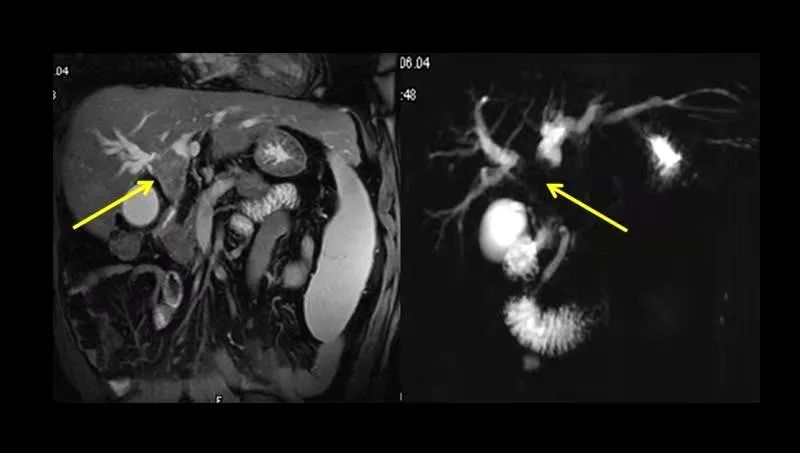

肝门部肿瘤MRI和MRCP图

MRCP,也叫磁共振胰胆管成像,是磁共振一种特殊成像方法,能快速直观地对整个胆道系统进行成像,可一目了然了解胆道疾病的部位和程度,现已广泛应用于临床。